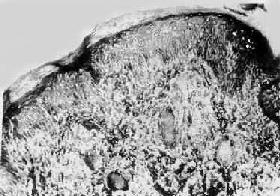

图18-17 结核样型麻风

真皮内有主由类上皮细胞构成的结节状病灶,其中可见Langhans细胞,颇似结核结节,但中央无干酪样坏死